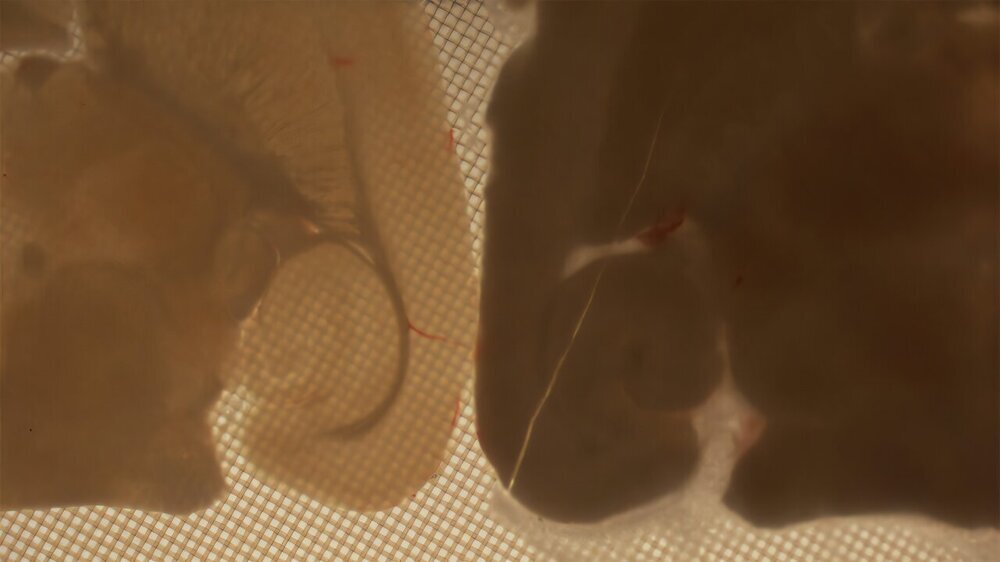

Команда FAU создала оптимизированный состав консервантов и тщательно разработала процесс охлаждения. Срезы гиппокампа грызуна охлаждали до -130 °C. Гиппокамп важен для памяти и обработки информации, что делает его идеальной моделью для проверки сохранности структуры и функции. После размораживания с помощью электронной микроскопии исследователи убедились, что наноструктура ткани не повреждена.